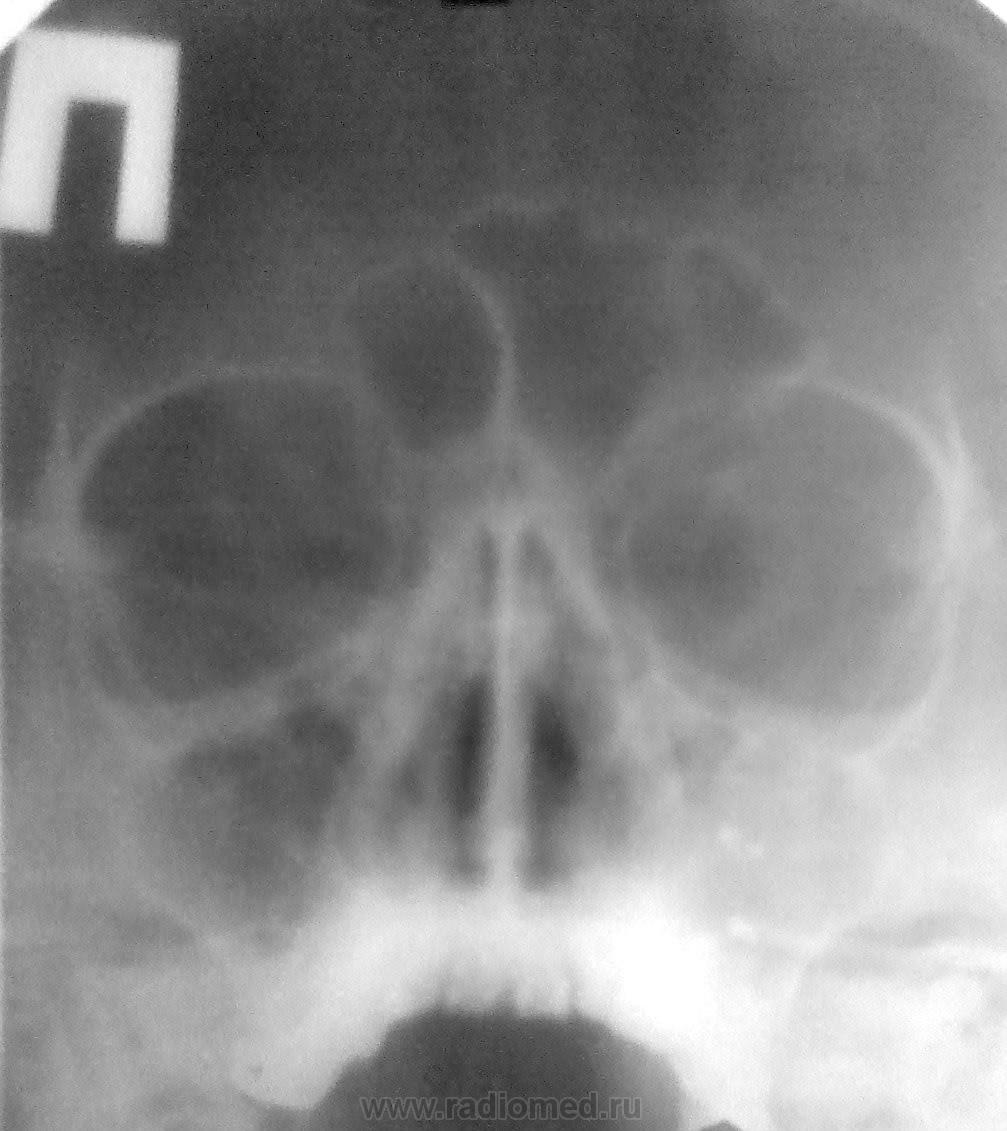

Пол пациента: Женский пол Тип патологии: Другое Область исследования: Челюстно-лицевая область и шея Молодая женщина. Диагноз при направлении - "хронический левосторонний гайморит" В принципе все ясно, но поскольку, как говорится, "есть варианты", то хотелось бы услышать мнение коллег https://radiomed.ru/sites/default/files/styles/case_slider_image/public/user/2667/v2v.jpg?itok=x51CXrcG https://radiomed.ru/sites/default/files/styles/case_slider_image/public/user/2667/v3v.jpg?itok=iK9ItfJZ ID:29230 Чт, 06/06/2013 - 16:05 #1 А.Ю. Не на сайте Был на сайте: 11 лет 10 месяцев назад Зарегистрирован: 03.10.2012 - 08:43 Публикации: 10 В области зуб 2.7 выведен пломбировочный материал в области ВЧП, вокруг пл.материала вероятнее всего образуются мицетомы. Одонтогенный левосторонний гайморит. Мицетома левой ВЧП. Конультация ЧЛХ. Чт, 06/06/2013 - 18:33 #2 stovbav Не на сайте Был на сайте: 2 года 2 месяцев назад Зарегистрирован: 20.12.2009 - 17:28 Публикации: 7066 Ну вот....уже "вариантов" и нет))))....Вы практически дословно повторили мое заключение)))) Болезни ног: виды, симптомы, причины, профилактика и лечение Чт, 06/06/2013 - 20:33 #3 Катенёв Валенти... Не на сайте Был на сайте: 7 лет 1 неделя назад Зарегистрирован: 22.03.2008 - 22:15 Публикации: 54876 Красивое подтверждение. Чт, 06/06/2013 - 20:34 #4 Катенёв Валенти... Не на сайте Был на сайте: 7 лет 1 неделя назад Зарегистрирован: 22.03.2008 - 22:15 Публикации: 54876 Мицетому тоже выставили в заключении Виктор Григорьевич? Чт, 06/06/2013 - 20:46 #5 stovbav Не на сайте Был на сайте: 2 года 2 месяцев назад Зарегистрирован: 20.12.2009 - 17:28 Публикации: 7066 Катенёв Валентин Львович wrote: Мицетому тоже выставили в заключении Виктор Григорьевич? Написал буквально так в конце протокола:" Прошу учесть возможность развития на этом фоне мицетомы". Болезни ног: виды, симптомы, причины, профилактика и лечение Пт, 07/06/2013 - 17:08 #6 И.Бондаренко Не на сайте Был на сайте: 3 дня 4 часа назад Зарегистрирован: 13.09.2011 - 22:55 Публикации: 9206 Понимаю, что мицетома грибы, но как её можно выставить? Во рту много разной бяки. Пт, 07/06/2013 - 17:40 #7 stovbav Не на сайте Был на сайте: 2 года 2 месяцев назад Зарегистрирован: 20.12.2009 - 17:28 Публикации: 7066 И.Бондаренко wrote: Понимаю, что мицетома грибы, но как её можно выставить? Во рту много разной бяки. Рентгенологически - да практически никак...но, учитывая то, что на ТАКОМ фоне это бывает, то на эту возможность внимание и акцентировано. Болезни ног: виды, симптомы, причины, профилактика и лечение

В области зуб 2.7 выведен пломбировочный материал в области ВЧП, вокруг пл.материала вероятнее всего образуются мицетомы. Одонтогенный левосторонний гайморит. Мицетома левой ВЧП. Конультация ЧЛХ.